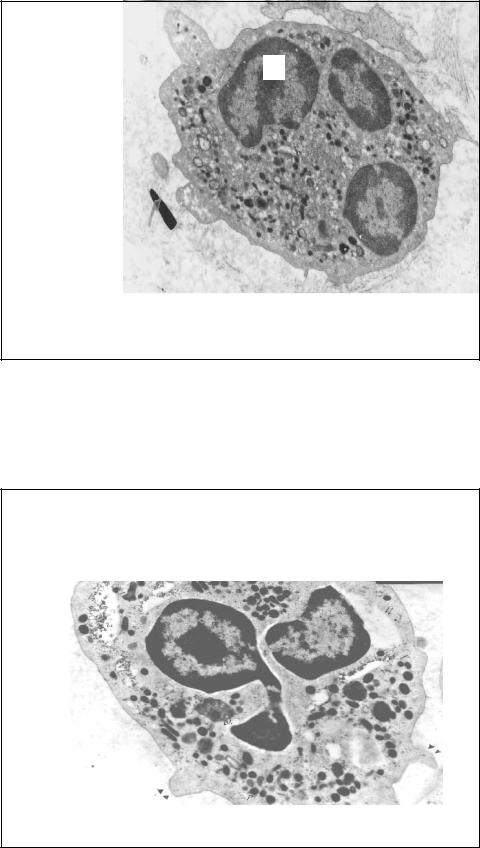

Нейтрофил, TЭM, x10,000

Ультраструктурные исследования показали, что вторичные гранулы варьируют по размерам, плотности и форме и что они содержат вещества, способствующие иммобилизации медиаторов воспаления и активации комплемента. Эти вещества секретируются во внеклеточное пространство. Третичные гранулы описаны недавно, они содержат ферменты (желатиназу, катепсин Д), способны вставлять некоторые гликопротеины в клеточные мембраны, что может способствовать клеточной адгезии и вконечном счете – фагоцитозу65.

Цитоплазма

нейтрофила содержит и другие органеллы помимо гранул: ГЭС, рибосомы и даже остатки комплекса Гольджи, который был хорошо развит, когда во время дифференциров ки участвовал в

66

упаковке гранул.

N

Нейтрофил, ТЭМ

Митохондрий у нейтрофила мало, они обеспечивают |

потребности в энергии лишь на 50%. |

После активации нейтрофилы часто оказываются в условиях нехватки кислорода и глюкозы. Поэтому они накапливают большое количество гликогена (gl) для анаэробного гликолиза. Энергия образуется в гексозо-монофосфатном шунте, но она используется в основном для продукции антимикробных оксидантов, нежели для внутренних потребностей клетки. Lysлизосомы, ag – азурофильные гранулыI .